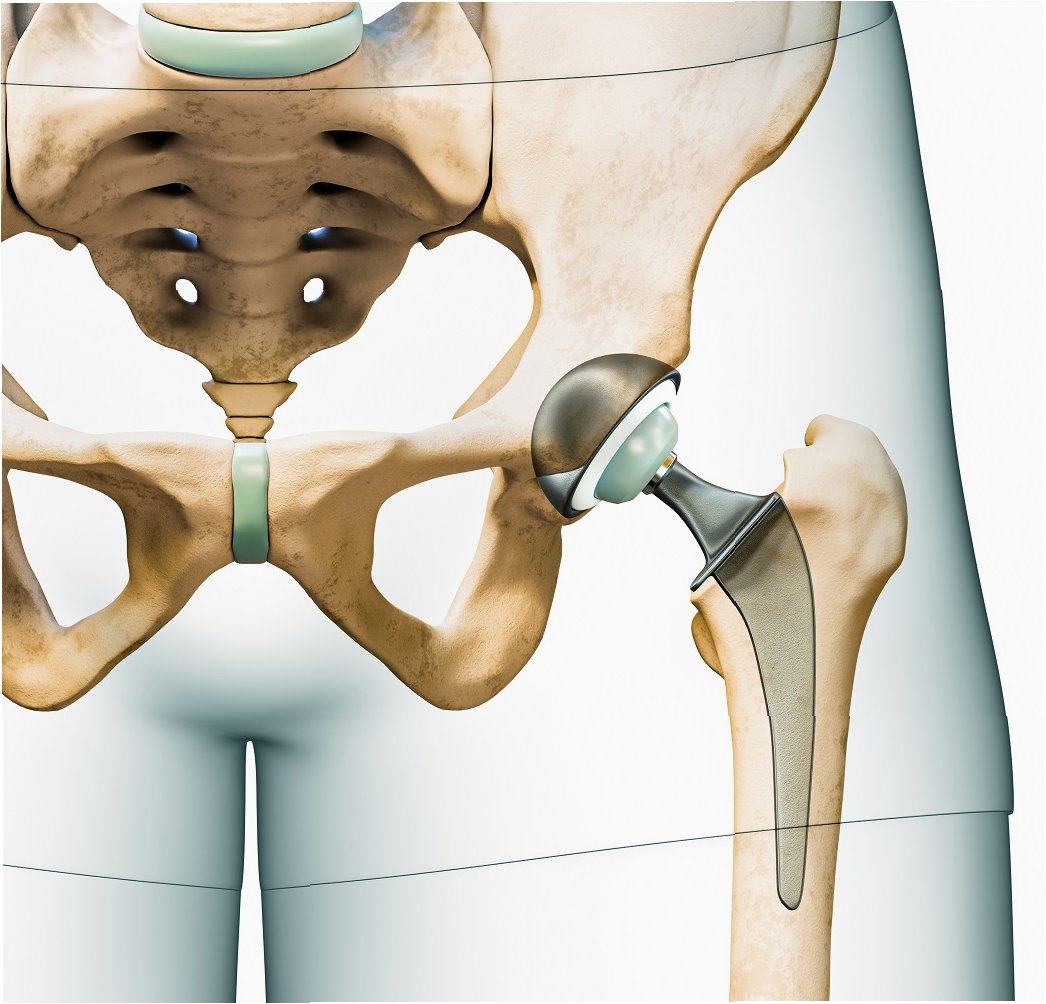

관절은 우리 몸의 움직임을 가능하게 하는 중요한 부분입니다. 하지만 관절 연골이 손상되거나 닳아 없어지면 극심한 통증과 함께 일상생활에 큰 불편함을 겪게 됩니다. 이러한 경우, 인공관절수술은 삶의 질을 향상시키는 효과적인 치료 방법이 될 수 있습니다. 인공관절수술은 손상된 관절을 인공관절로 대체하여 통증을 완화하고 관절의 기능을 회복시키는 것을 목표로 합니다. 수술 후에는 보다 자유롭고 활동적인 생활을 누릴 수 있으며, 긍정적인 심리적 변화도 기대할 수 있습니다. 인공관절수술은 단순히 통증을 없애는 것을 넘어, 환자가 건강하고 행복한 삶을 되찾도록 돕는 중요한 과정입니다.

인공관절수술은 다양한 관절 질환에 적용될 수 있습니다. 대표적인 질환으로는 퇴행성 관절염, 류마티스 관절염, 외상 후 관절염 등이 있습니다.

인공관절수술은 일반적으로 손상된 관절 부위를 절개하고, 손상된 뼈와 연골을 제거한 후 인공관절을 삽입하는 방식으로 진행됩니다. 수술 시간은 관절 부위, 수술 방법, 환자의 상태에 따라 다르지만, 대개 1~3시간 정도 소요됩니다. 수술 후에는 통증 관리와 함께 조기 재활 운동을 시작하여 관절의 기능 회복을 돕습니다. 초기에는 보행 보조기구(목발, 보행기 등)를 사용하며, 점차적으로 사용 빈도를 줄여나갑니다. 재활 운동은 관절의 가동 범위를 늘리고 근력을 강화하여 일상생활 복귀를 돕는 데 매우 중요합니다. 회복 기간은 개인의 상태, 수술 방법, 재활 노력에 따라 다르지만, 일반적으로 수술 후 3~6개월 이내에 일상생활로의 복귀를 목표로 합니다. 꾸준한 재활과 관리를 통해 건강한 관절 기능을 회복하고 오랫동안 유지할 수 있습니다.